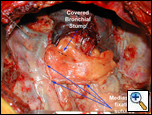

| Figure 1: Buttress of esophageal suture line at post-operative day 10. |

Buttressing suture/staple lines in thoracic surgery has been shown to promote healing and prevent breakdown, especially in situations where the native tissues have been compromised. There are a wide variety of tissue flaps that have been used within the chest ranging from pleura, muscle, to omentum [1]. The pericardial fat pad flap is a reliable buttress of a bronchial, pulmonary arterial or esophageal suture line (Figure 1) [2].